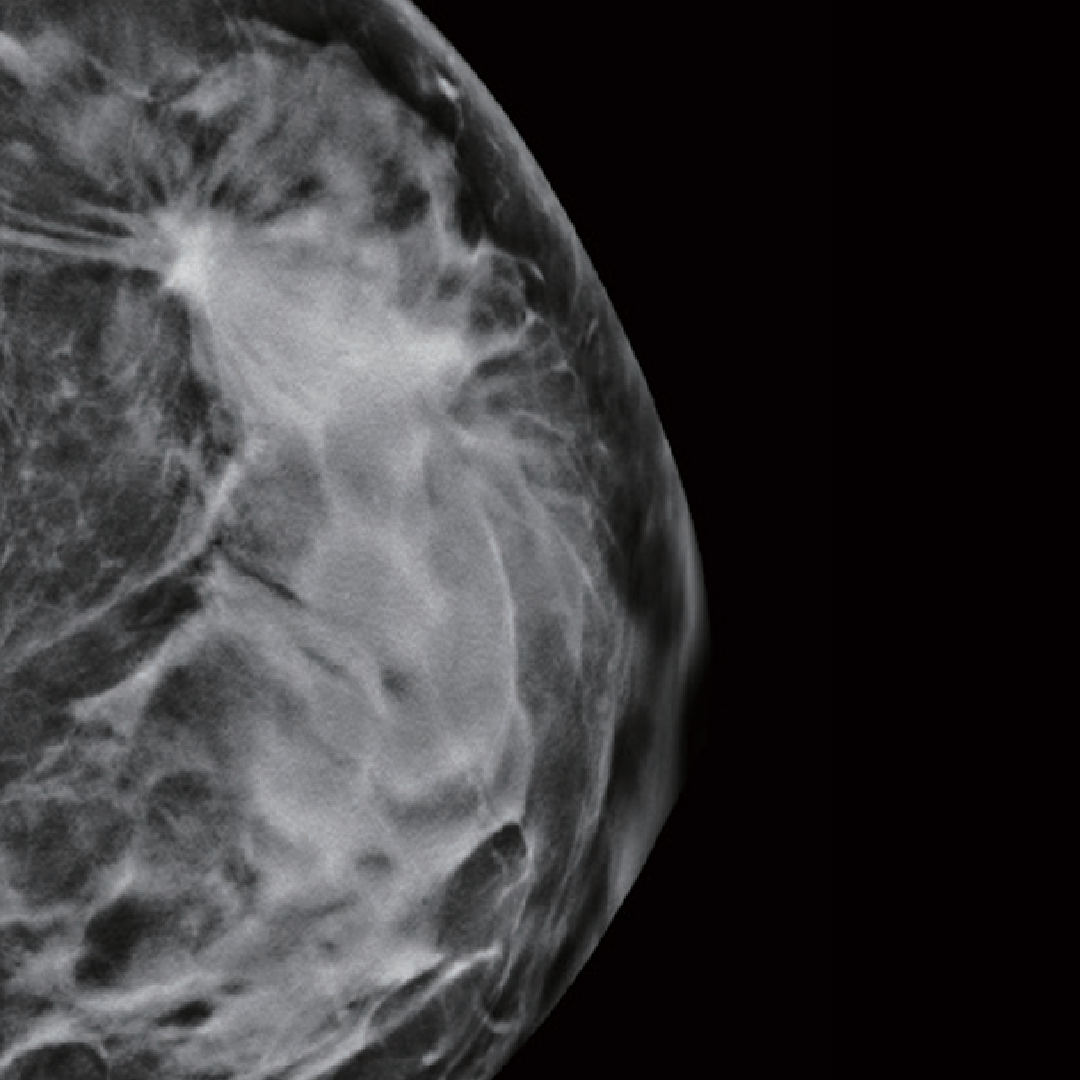

Mamografía digital de campo completo con tomosíntesis

Tomosíntesis avanzada para diagnósticos más certeros, incluso en mamas densas o casos difíciles.

Imágenes ultradefinidas gracias a su resolución de 16 bits

Escaneo de 50° en solo 8 segundos: velocidad y precisión en cada toma

Tomosíntesis 3D con detector avanzado y tubo de alta precisión

Tomosíntesis avanzada con potencia y precisión: imágenes más claras, diagnósticos más certeros.